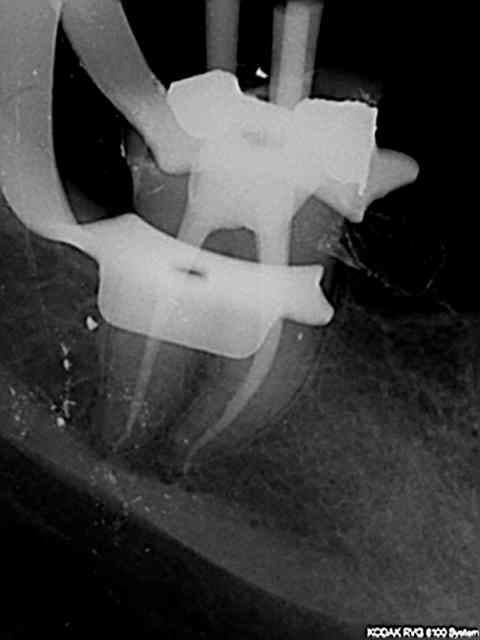

J'ai utilisé le localisateur d'apex , mais bon un radio c'est une radio ...)))

Mais pas la digue , c'est vrai .

Je rassure tout le monde , j'ai travaillé sans digue , mais je jure sur l'honneur que pas un nanogramme de salive ne contamina cette dent , sinon , hin ...